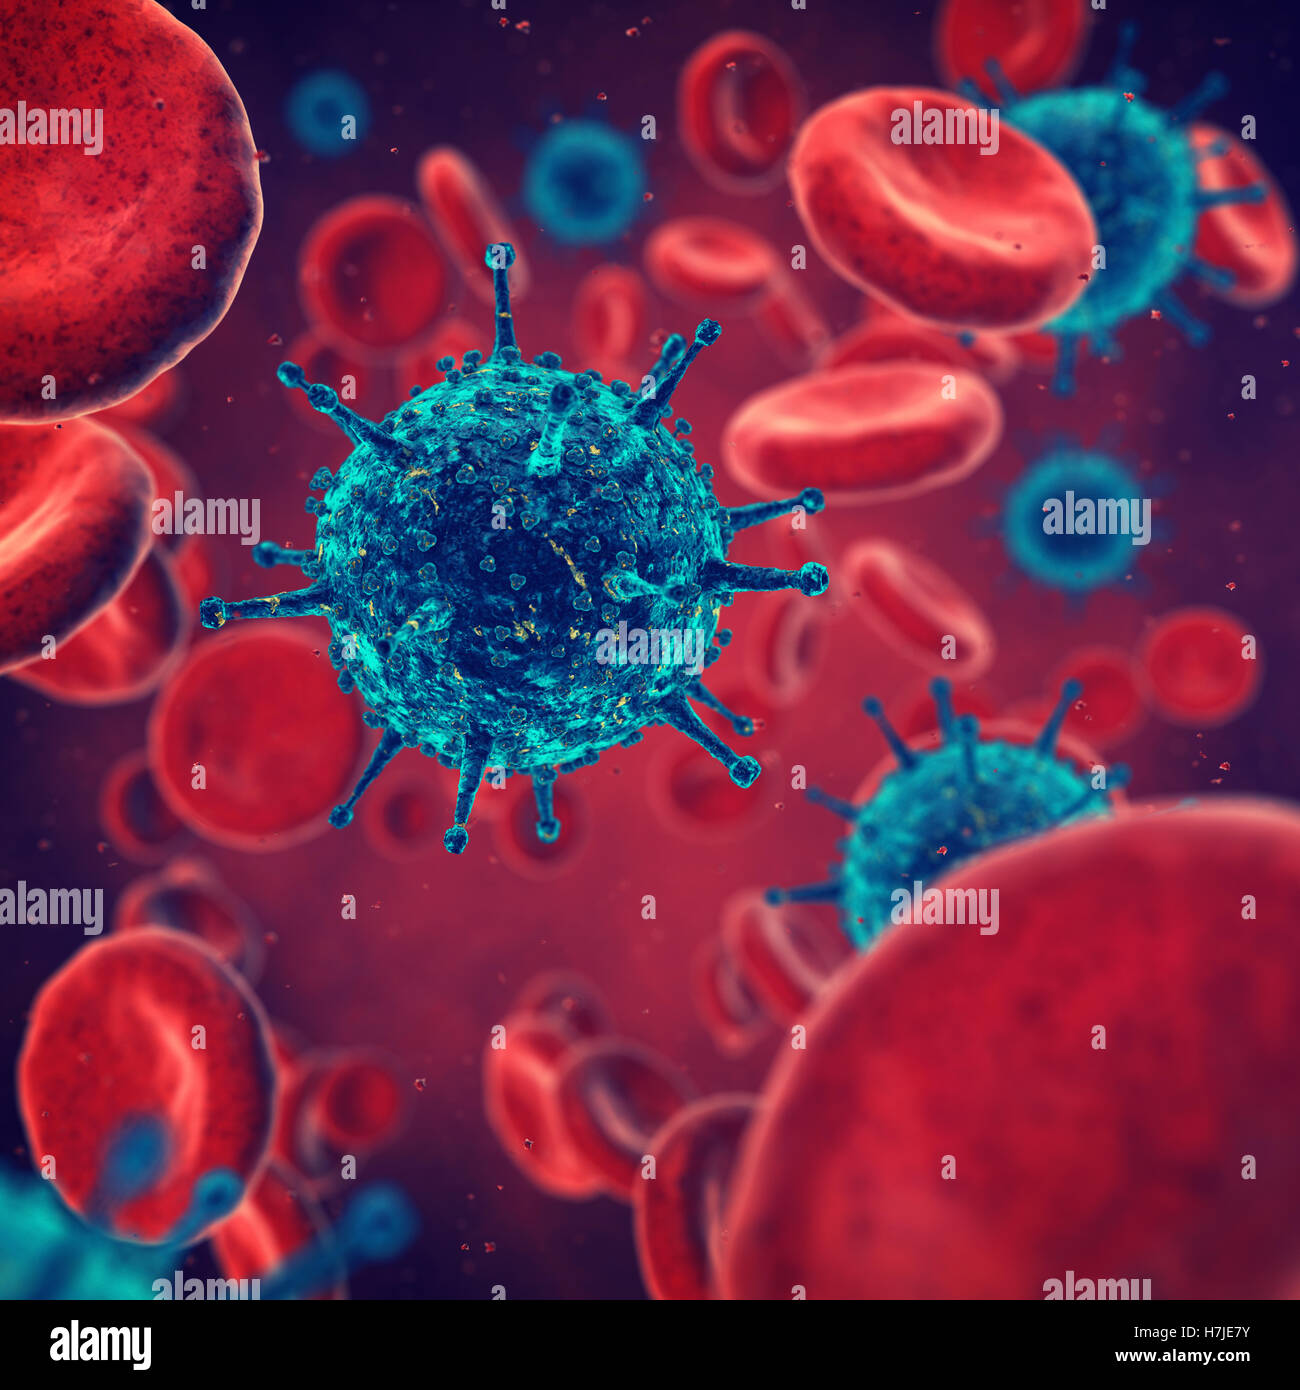

Viruses and red blood cells , contaminated blood , Disease Stock Photohttps://www.alamy.com/image-license-details/?v=1https://www.alamy.com/stock-photo-viruses-and-red-blood-cells-contaminated-blood-disease-125181503.html

Viruses and red blood cells , contaminated blood , Disease Stock Photohttps://www.alamy.com/image-license-details/?v=1https://www.alamy.com/stock-photo-viruses-and-red-blood-cells-contaminated-blood-disease-125181503.htmlRFH7JE7Y–Viruses and red blood cells , contaminated blood , Disease

Viruses and red blood cells , contaminated blood , Disease Stock Photohttps://www.alamy.com/image-license-details/?v=1https://www.alamy.com/stock-photo-viruses-and-red-blood-cells-contaminated-blood-disease-102886110.html

Viruses and red blood cells , contaminated blood , Disease Stock Photohttps://www.alamy.com/image-license-details/?v=1https://www.alamy.com/stock-photo-viruses-and-red-blood-cells-contaminated-blood-disease-102886110.htmlRFFYAT7X–Viruses and red blood cells , contaminated blood , Disease